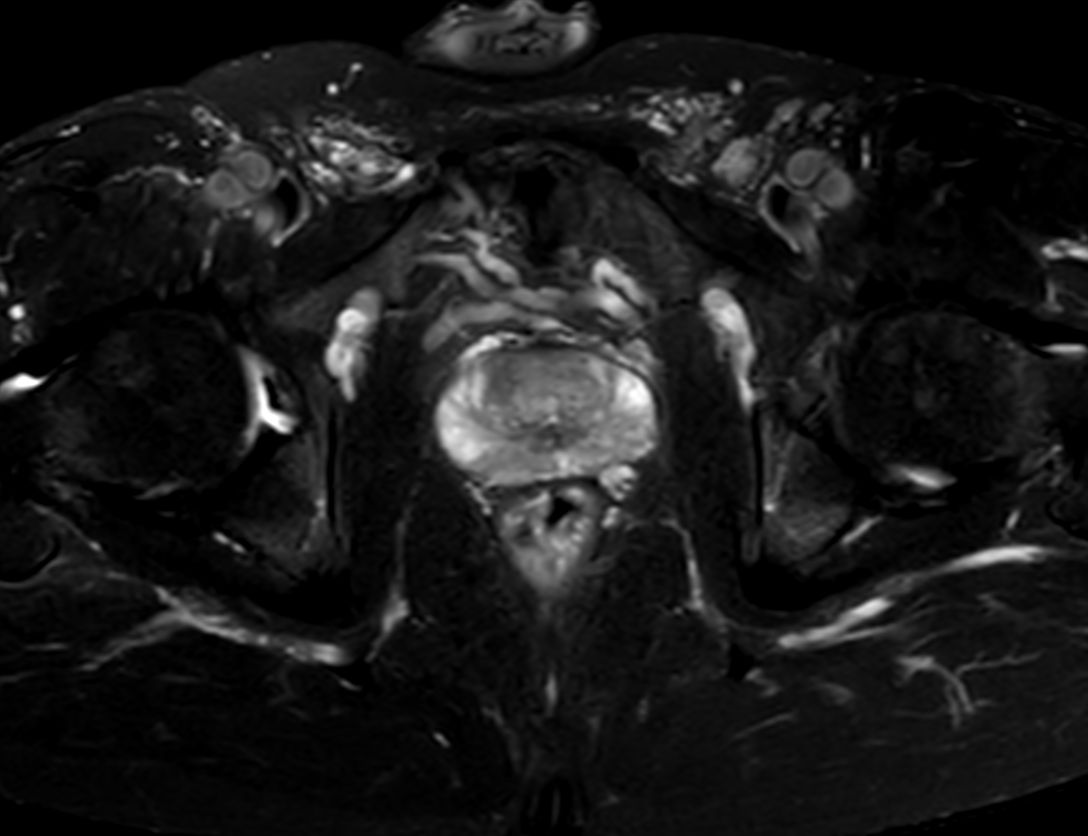

For prostate exams, the MSK M coil can be used in combination with the posterior coil, delivering exceptional quality MR images and high patient satisfaction.

Premium signal-to-noise ratio is achieved via dStream, providing outstanding image resolution.

ScantimeObjective